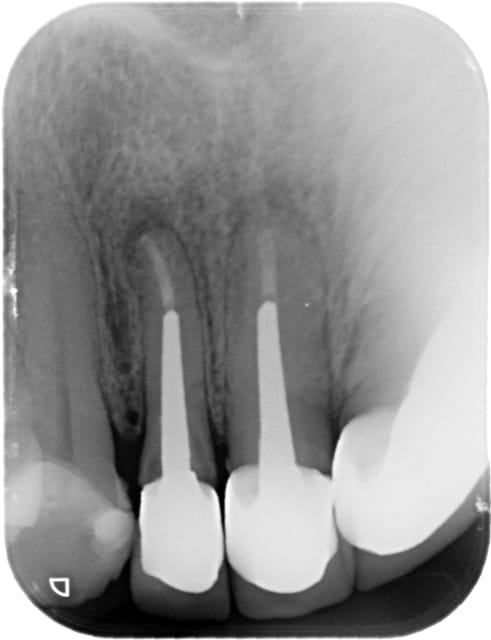

une autre 22.

lésion apicale avec fistulisation il y a quelques semaines.

1/ Dépose de la couronne à tenon dans le cadre d'une réhabilitation prothétique globale des prothèses car racines marrons apparentes dans le sourire. odeur --- rockles sur coton. pansement.

radio post OP. et la le doute , la raison de mon post...

image hélicoïdale à l'apex.

je vérifie le lentulo, je le compare avec ses semblables.

Il ne manque rien.

La pâte à laissé la trace du lentulo on jurerait qu'il y en a un bout, vous confirmez? vous avez déjà remarqué ça ?

Je ne vois pas de lentulo, par contre ça ressemble à un dépassement de cône de gutta.

Hors sujet peut être, mais faudrait aussi traiter la 21, et vu le délabrement radiculaire cervical prévoir une bonne élongation coronaire pour 22 et 21, et sensibiliser le patient à l'implanto, car à mon avis c'est pour bientôt.